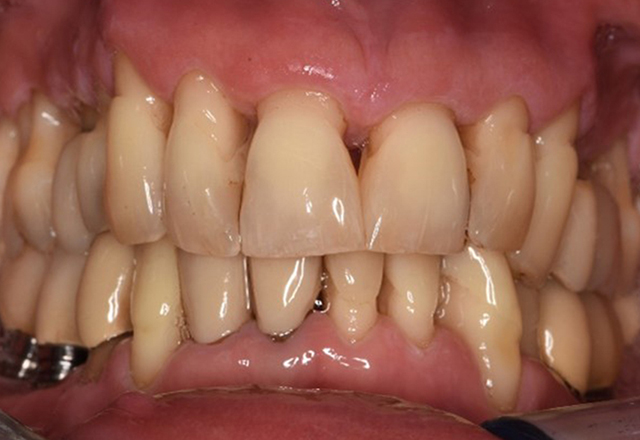

The healthy patient with pre-existing periodontal disease & peri-implantitis

A 52-year-old patient presents at a preventive care session. The patient has no systemic disease and is not taking any medication. He has had various dental treatments and also has two active carious lesions. In addition, the patient has four implants (2nd, 3rd and 4th quadrants). He is revealed to have early periodontal disease (stage IV, grade B). His periodontal condition is stable; a probing depth of Probing depths (ST) of 5 mm is only evident at the implant in region 36. Gingivitis is also identified. more